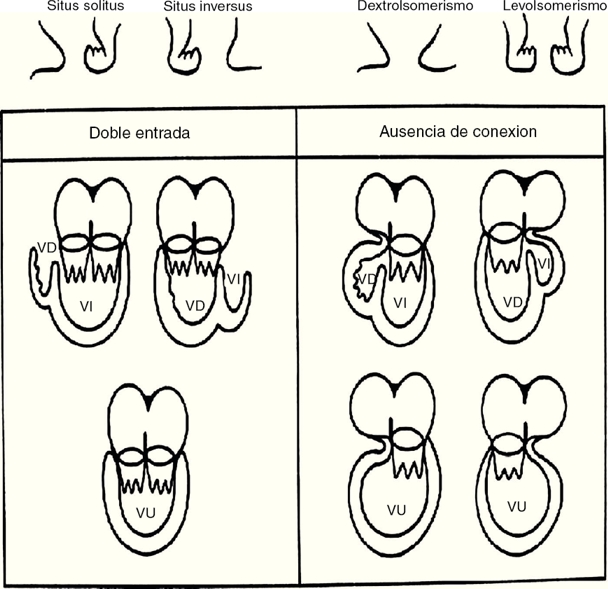

La doble entrada ventricular es un tipo de conexión auriculoventricular univentricular en la que ambas aurículas se abren a un solo ventrículo y presenta 3 modalidades: en ventrículo izquierdo5, en ventrículo derecho6 y en ventrículo único a través de 2 válvulas auriculoventriculares o de una válvula auriculoventricular común7,8 (Figs. 2 y 3).

Figura 3 Vista interna del ventrículo derecho con doble entrada a esta cámara. Obsérvese la válvula auriculoventricular común conectada en más del 75% con el ventrículo derecho. Ao: aorta; AP: arteria pulmonar; VC: válvula común; VD: ventrículo derecho. Asterisco: comunicación interventricular.

Se define al ventrículo único cuando existe en la masa ventricular una sola cámara que en su porción de entrada presenta la conexión auriculoventricular y en su porción de salida emergen las grandes arterias o una sola arteria, el tronco aórtico solitario9,10 (Fig. 4).